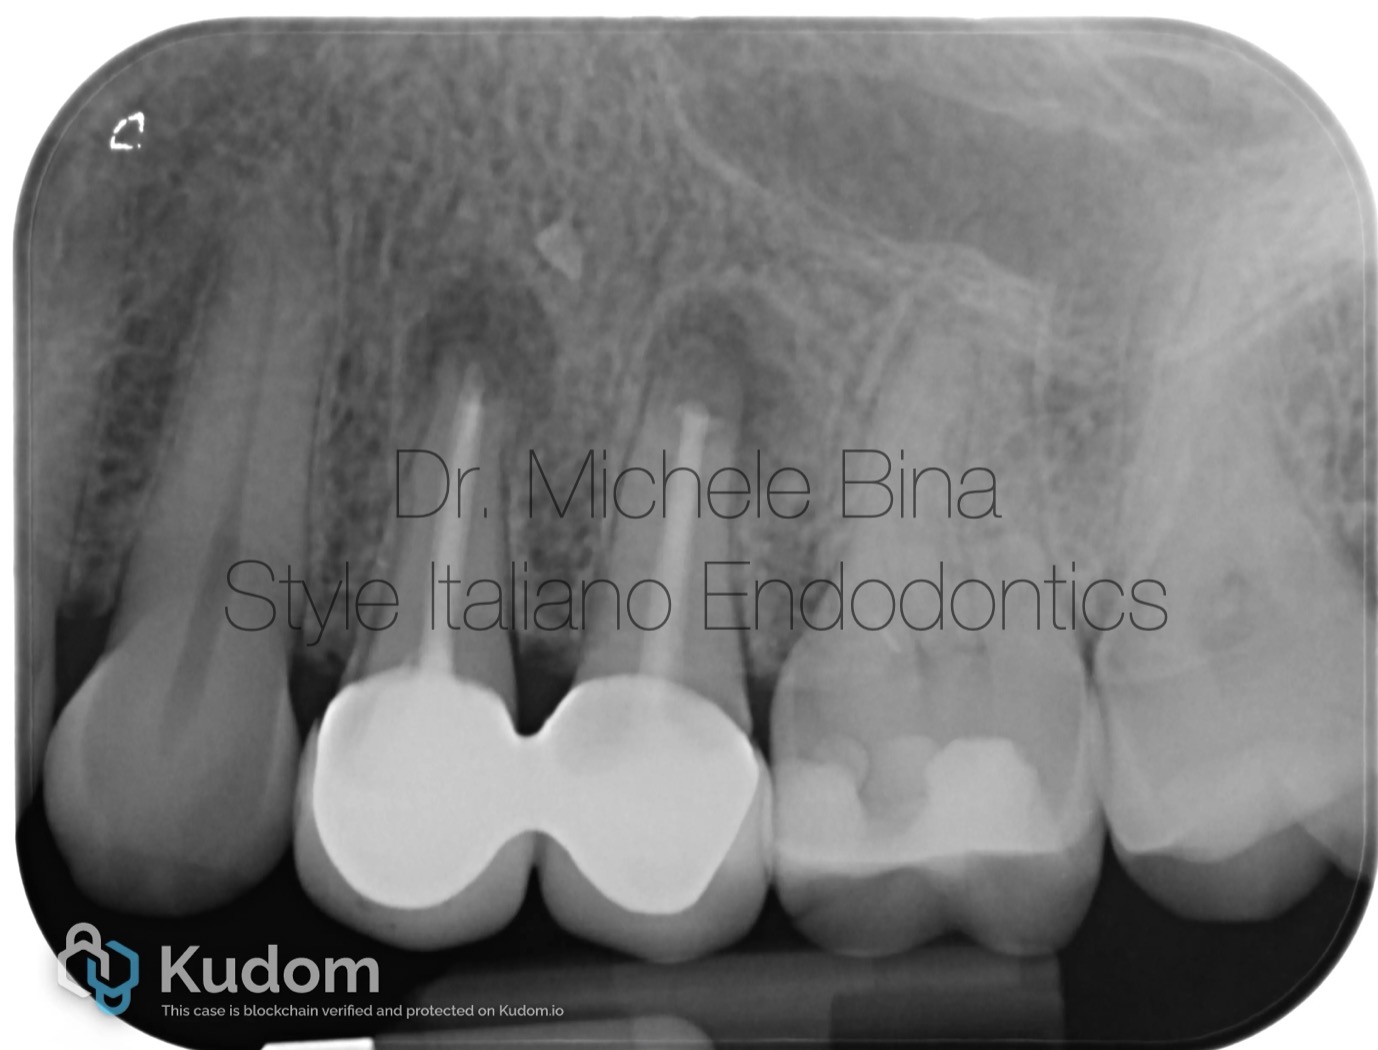

Post operative rx

Fig. 3